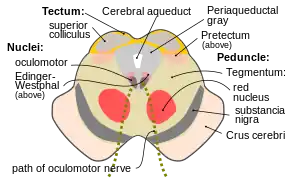

Section through superior colliculus showing path of oculomotor nerve. (Tegmentum not labeled, but surrounding structures more clearly defined.) | |

The midbrain is anatomically delineated into the tectum (roof) and the tegmentum (floor). The midbrain tegmentum extends from the substantia nigra to the cerebral aqueduct in a horizontal section of the midbrain. It forms the floor of the midbrain that surrounds below the cerebral aqueduct as well as the floor of the fourth ventricle while the midbrain tectum forms the roof of the fourth ventricle. The tegmentum contains a collection of tracts and nuclei with movement-related, species-specific, and pain-perception functions. The general structures of midbrain tegmentum include red nucleus and the periaqueductal grey matter.

Unlike the midbrain tectum (which is a sensory structure located posteriorly), the midbrain tegmentum, which locates anteriorly, is related to a number of motor functions. Within the tegmentum, the red nucleus is in charge of motor coordination (specifically for limb movements) and the periaqueductal gray matter (PAG) contains critical circuits for modulating behavioral responses to pains. The substantia nigra (black substance) serves an important role in rewarding behaviors such as approaching desired objects. In addition, the substantia nigra forms reciprocal connections with the basal ganglia which are highly correlated with motor functions and learning.